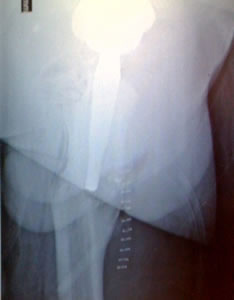

He was in his usual state of good health until age 14 when he became spontaneously septic. He was placed on ID pressors and subsequently lost his toes from vasoconstriction. He developed AVN of the femoral head. He does not think he was on any prednisone. He was then treated with a hip fusion. During the hip fusion the surgeon decided to do a subtrochanteric osteotomy which left the patient with a deformed proximal femur. He was placed in a hip spica cast for over 5 months. He believes he was also infected in the cast, but after speaking to him it sounds as if he had wound breakdown from the cast and not a deep infection.

| Distal canal reamers encounter a bony bridge which was anticipated so intra-operative decision confirmed pre-operative plan to shorten the stem implant length. |

| Apex Modular Stem was used that features a special “Dual Press” modular junction. This design allows for selection of a variety of femoral offsets and one of three version angles: Neutral or 13º of anteversion or retroversion. |

| Pre-operative consideration was discussed on shorting the stem to avoid any potential femoral canal perforations. For this reason a special proximal modular stem “Dual-Press” design was utilized. Proximal conical reaming was done without the use of a pilot shaft along with rasping of the femoral triangle. |

Careful intra-operative measurements were done then surgery on the stem to customize “shortening of the stem” stem length. |

| You will notice when you take out the pelvic obliquity it is 45 degrees |